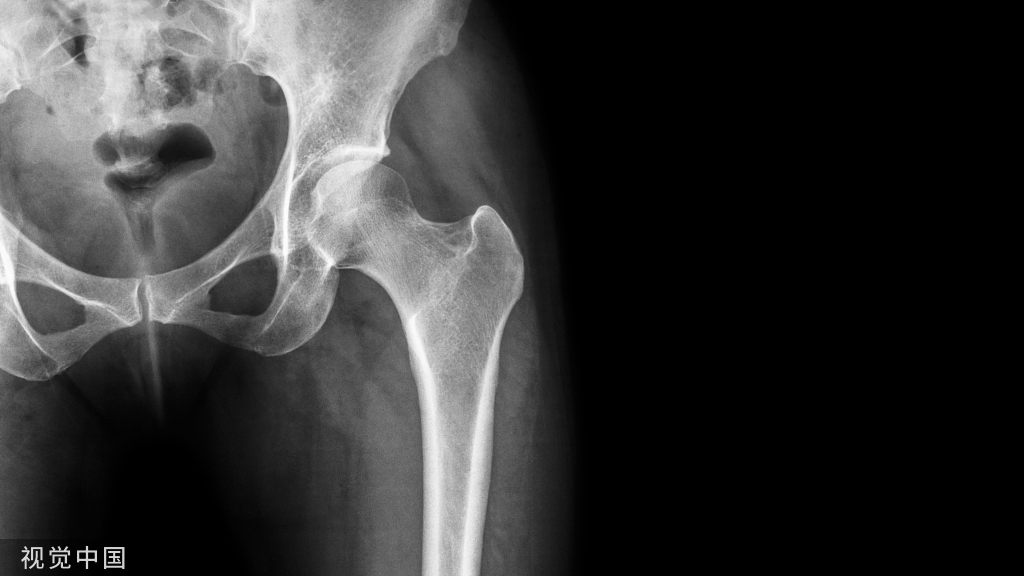

1%-9%的高能量股骨干骨折合并隐匿性同侧股骨颈骨折,隐匿性股骨颈骨折通常无移位,且19%-55%的隐匿性骨折在影像片上无阳性表现。

未明确诊断的股骨颈骨折,可能会导致计划外的二期手术,因此有学者建议对所有高能量股骨干骨折患者预防性固定股骨颈,但该方法显然并不经济。也有学者建议对所有高能量患者进行股骨颈MR扫描,但MR扫描等待时间长,费用高等仍使其临床应用受限。针对上述问题,有学者探讨在CT影像上,股骨颈骨折表现的关节积脂血症(lipohemarthrosis对股骨颈骨折的预测上是否存在价值。

本研究的目的是研究对CT上伴有髋关节积脂血症形成表现的囊性征作为术前髋关节磁共振成像(MRI)或同侧股骨颈预防性固定的选择性指标的有效性,以预防因高能量股骨干骨折患者同侧隐匿性股骨颈骨折延迟诊断而导致的计划外手术。